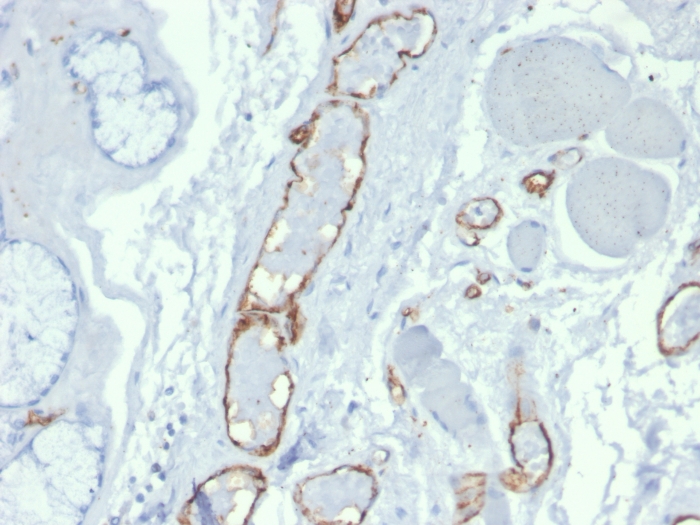

Formalin-fixed, paraffin-embedded human prostate stained with CD31 Mouse Monoclonal Antibody (PECAM1/3527).

CD31 (PECAM-1) is a transmembrane glycoprotein member of the immunoglobulin supergene family of adhesion molecules. CD31 is expressed by stem cells of the hematopoietic system and is primarily used to identify and concentrate these cells for experimental studies as well as for bone marrow transplantation. Anti-CD31 has shown to be highly specific and sensitive for vascular endothelial cells. Staining of nonvascular tumors (excluding hematopoietic neoplasms) is rare. CD31 MAb reacts with normal, benign, and malignant endothelial cells which make up blood vessel lining. The level of CD31 expression can help to determine the degree of tumor angiogenesis, and a high level of CD31 expression may imply a rapidly growing tumor and potentially a predictor of tumor recurrence.